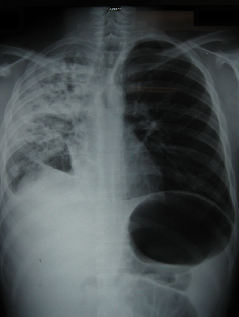

A 10-month-old girl was admitted to the hospital with complaints of fever, cough, and fast breathing for 5 days.

Zachary Obinna Enumah, MA; Jeffrey M. Chinsky, MD, PhD

A 16-year-old boy presented to the emergency department after being referred by his primary care physician for having failed outpatient therapy for pneumonia.